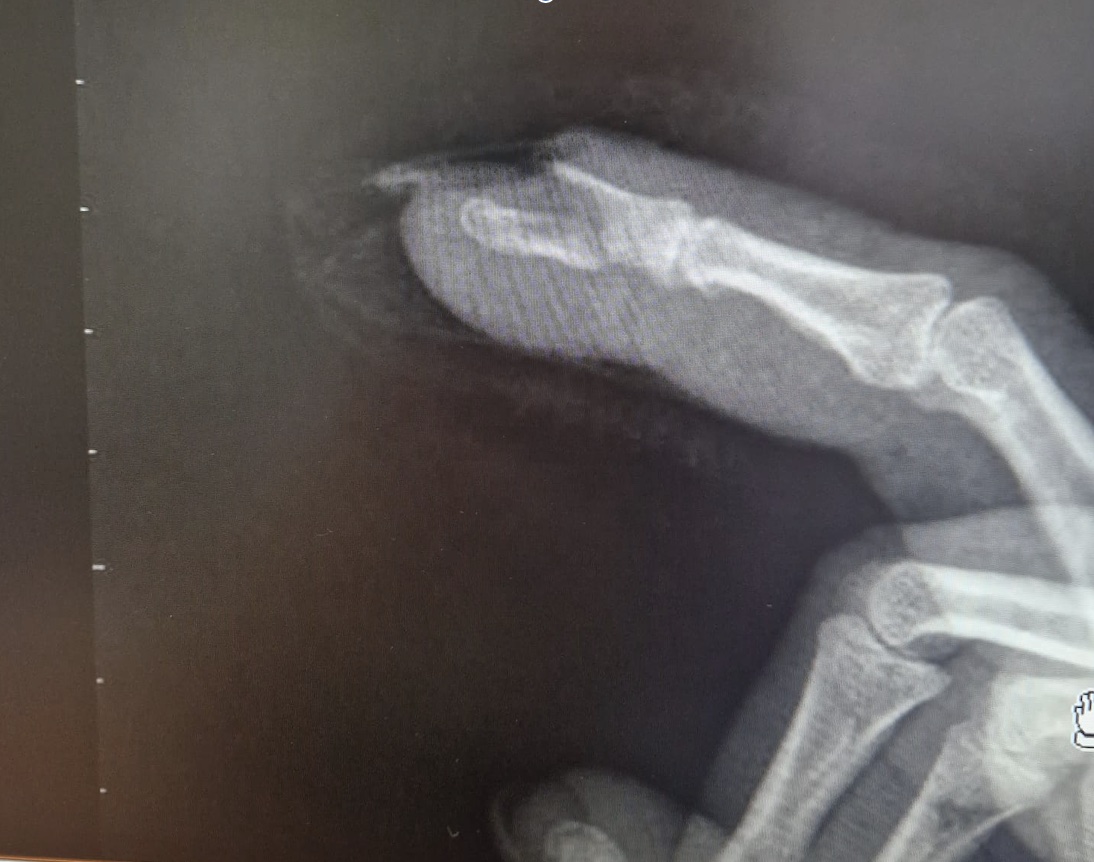

Pruebas complementarias

Se decide derivación a urgencias donde confirman fractura mediante radiografía de la mano.

Juicio clínico, diagnóstico diferencial, identificación de problemas

Juicio clínico: Fractura desplazada de falange distal 2º dedo mano derecha.